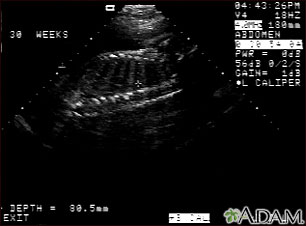

A pregnancy ultrasound is an imaging test that uses sound waves to create a picture of how a baby is developing in the womb (uterus). It is also used to check the female pelvic organs during pregnancy.

- These waves bounce off the body structures, including the developing baby, to create a picture on the ultrasound machine.

A pregnancy ultrasound may also be done in the second and third trimesters to:

- Determine the baby's age, growth, position, and sometimes sex.

- Identify any problems with how the fetus is developing.

- Look for twins or triplets. Look at the placenta, amniotic fluid, and pelvis.

The developing baby, placenta, amniotic fluid, and surrounding structures appear normal for the gestational age.